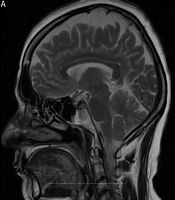

Renal Involvements in Children with Congenital Heart Disease

28

Oct

2025